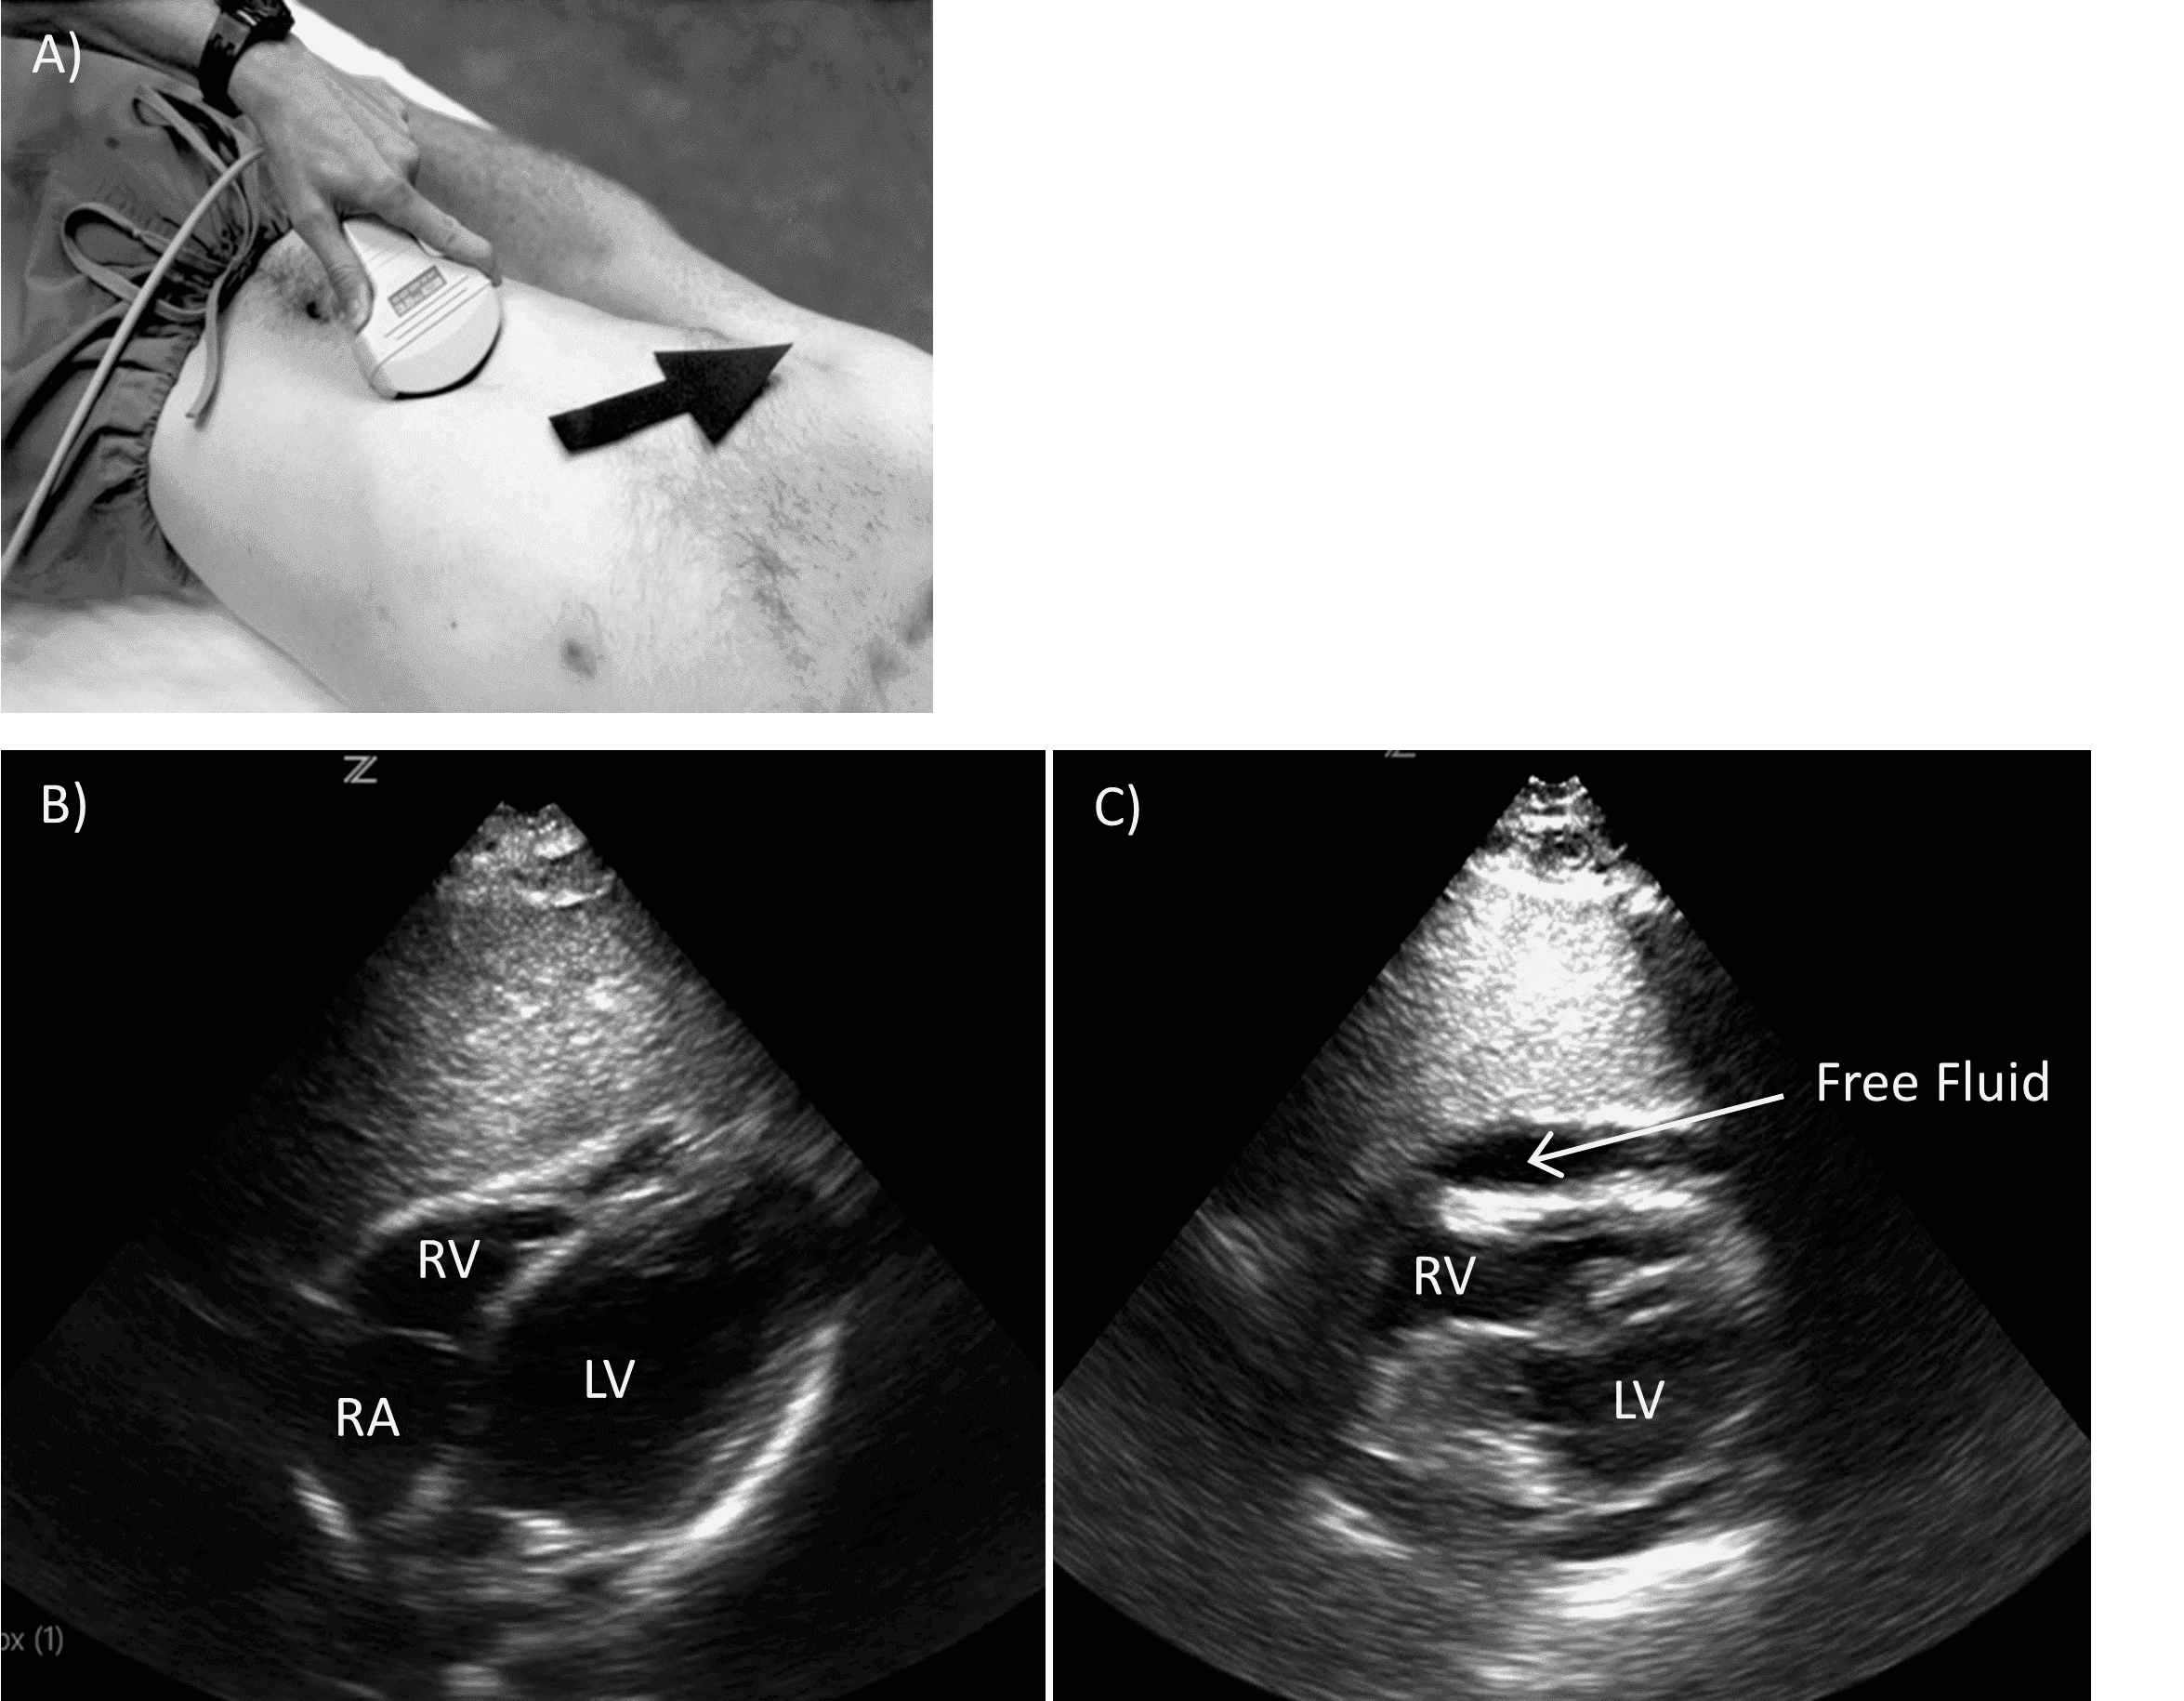

The pericardium is typically evaluated using a subxiphoid view. The curvilinear probe is placed in the subxiphoid region orientated transversely with the indicator pointed to the patient’s right. The probe is gently positioned under the xiphoid and fanned upward such that it nearly lies flat along the patient’s abdomen (Figure 2).

Subxiphoid Pericardial view.

A) Probe positioning. B) Normal view. C) Positive view with pericardial effusion.

RV (right ventricle), RA (right atrium), LV (left ventricle)

This typically does not require significant pressure and, if performed correctly, the patient should not feel significant discomfort with this maneuver. All four chambers of the heart should be visible. A pericardial effusion appears as an anechoic stripe. It is important to distinguish a pericardial effusion from the pericardial fat pad, which will move with the heart as it contracts. An effusion will not move. Patients with evidence of tamponade physiology may require immediate intervention, including thoracotomy or subxiphoid window.